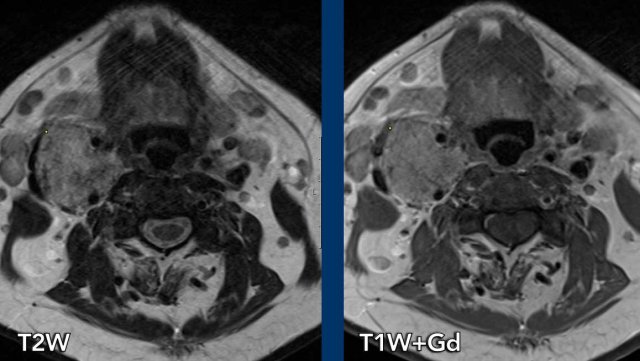

This young man was involved in a motocross accident.

He was admitted to the ICU with multiple injuries.

After three days he regained consciousness and a paresis of his right side was noted, which could not be explained by any cerebral injury.

He also had a Horner on the right side.

Images

The CT at admission showed fractures of the transverse process of C7 and of the first rib (arrowheads).

On the CECT there was contrast extravasation indicating active bleeding (circle).

Continue with the MRI...

First an ultrasound of the neck was performed to look for nerve avulsion, but this examination was limited by traumatic changes in this area.

Subsequently an MRI was performed.

The axial image shows enhancement of nerve roots indicative of a brachial plexus injury.

Also note the injury to the right paravertebral soft tissues.

Continue....

Image

In addition the T2W-image shows some subtle high signal in the myelum on the right (arrow).

This was regarded as post traumatic myelopathy and could also be an explanation for the right-sided Horner.